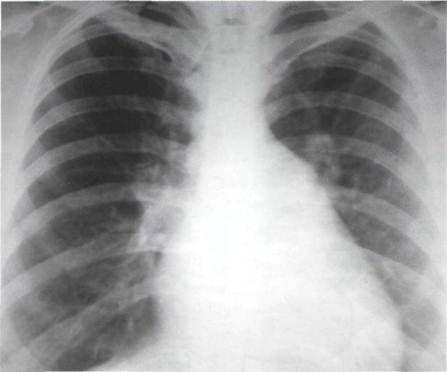

Недостаточность митрального клапана по сравнению с митральным стенозом отличается большими размерами сердца. Особенно значительно увеличиваются левое предсердие и левый желудочек. Преимущественное увеличение размеров этих полостей лежит в основе многих рентгенологических признаков митральной недостаточности.

Переднезадняя проекция

Правый атриовазальный угол часто смещен вверх. Но не из-за увеличения правых отделов сердца, а потому, что у этих больных в его образовании участвует выходящее на правый контур значительно увеличенное левое предсердие.

Для формы сердца при митральной недостаточности, как и при митральном стенозе, характерно отсутствие талии, однако при митральной недостаточности форма сердца отличается значительно большим разнообразием, т. к. зависит от направления, в котором происходит увеличение левого предсердия, что, в свою очередь, определяется локализацией дефекта в клапане и направлением струи регургитации крови. Часто отмечается резкое расширение третьей дуги левого контура, обусловленное перерастяжением ушка левого предсердия. Однако изменения левого контура нередко ограничиваются лишь выравниванием талии или незначительным выбуханием третьей дуги. Резкое увеличение левого предсердия преимущественно вправо образует добавочную дугу на правом контуре, отличающуюся от таковой при митральном стенозе большими размерами и гораздо большим расширением в правое легочное поле. Иногда контуры левого предсердия равномерно и резко расширены в обе стороны в верхних отделах сердечной тени, придавая сердцу сходство с «фигурой желудя». В других случаях огромное аневризматически расширенное левое предсердие прилегает к диафрагме справа или выступает влево в виде добавочного образования средостения . Вслед за увеличением размеров левого предсердия происходит расширение тени левого желудочка. Увеличение объема этой полости также зависит от степени регургитации крови через митральный клапан.